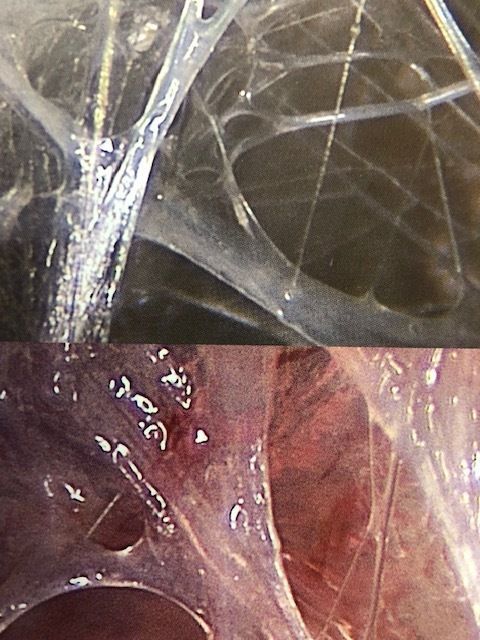

Faszien verbinden alle Körperstrukturen miteinander, umhüllen Organe, kleiden Körperräume aus. Sie verfügen über zahlreiche Mechanorezeptoren und haben damit die Fähigkeit zur Eigenwahrnehmung. Faszien können als eigenständiges Organsystem im Körper bezeichnet werden.

Der Begriff «Faszie» ist eine Bezeichnung für: Bänder, Sehnen, Sehnenplatten, Haltebänder, Gelenkkapseln, Organkapseln, Hirnhaut, Knochenhaut, Muskel Septen …

Weil die Faszien so vielfältig sind, können auch verschiedene Formen von Distorsionen entstehen, welche FDM/S. Typaldos wie folgt beschreibt und behandelt: